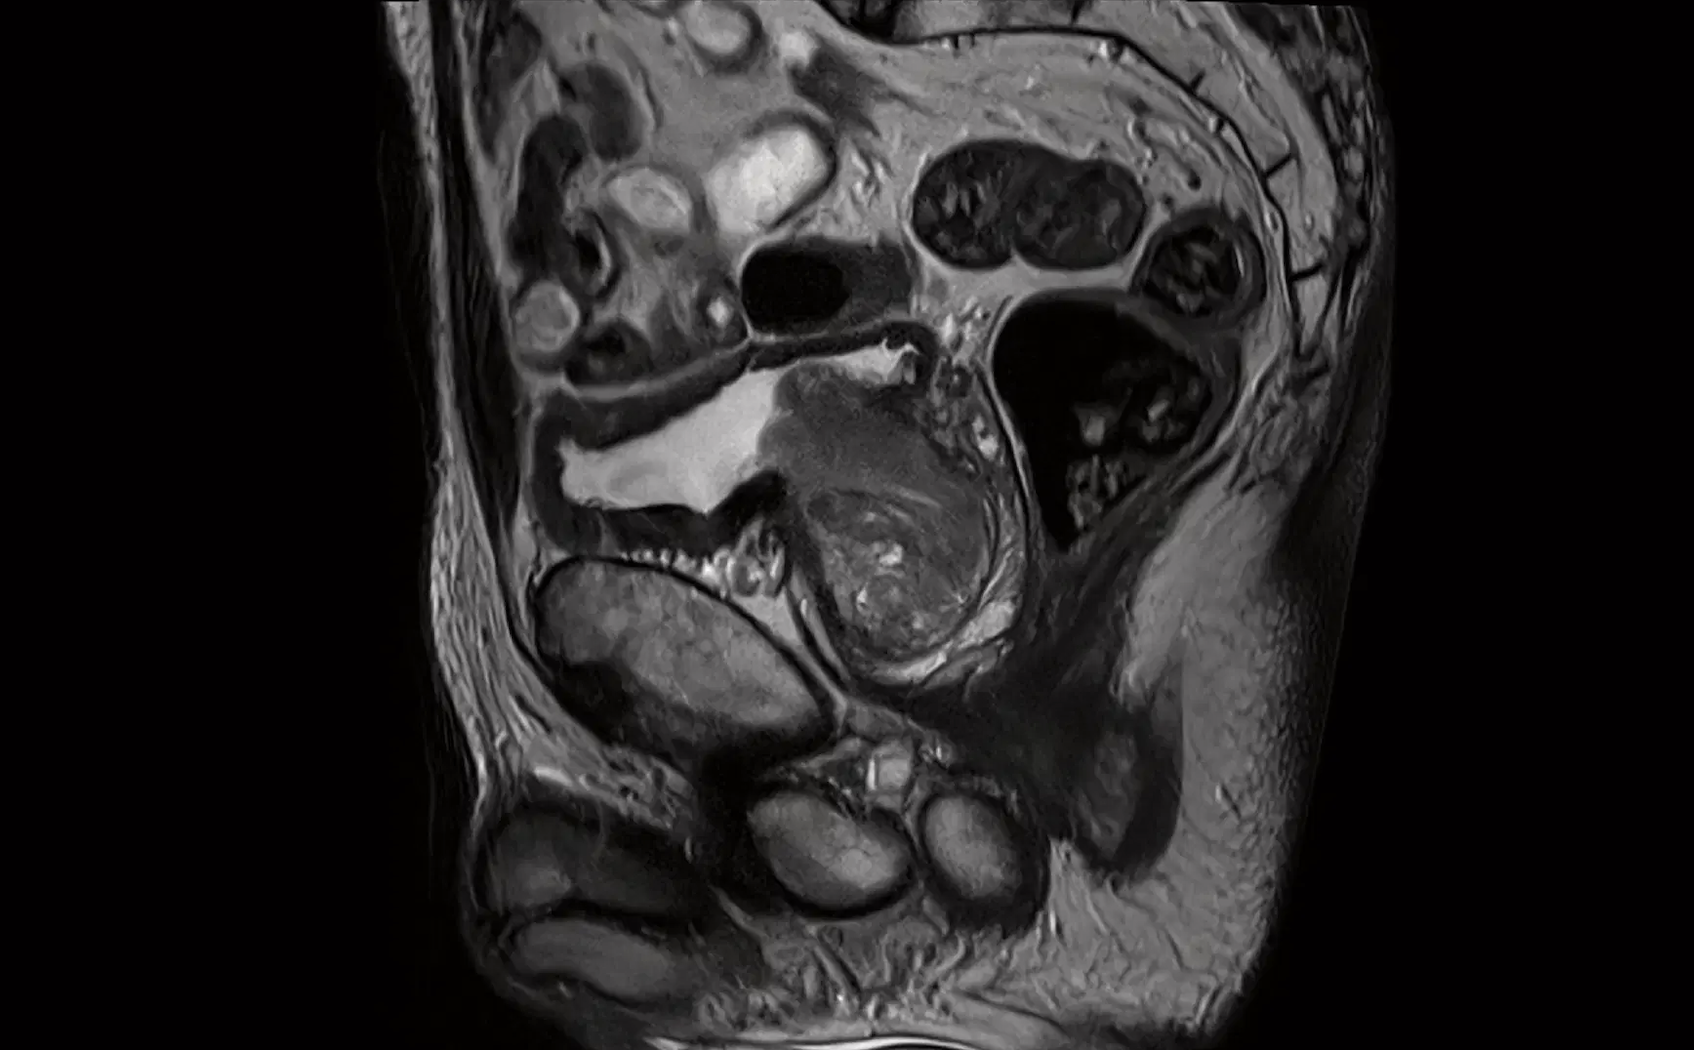

The Siemens Healthineers 3T Magnetom Cima.X. Faster scan time with Deep Resolve for TSE outruns motion and substantially shortens the prostate exam. Image courtesy of Siemens Healthineers

For its part, Siemens unveiled the 3T Magnetom Cima.X in December, 2022, at the annual meeting of the Radiological Society of North America (RSNA). The scanner offers unprecedented technical performance features when compared to conventional whole-body MRI systems in place now. A developmental scanner, the Cima is not yet commercially available. According to a Texas A&M Today article (January 2023 by Adrena Dow, of Texas A&M School of Engineering Medicine), the scanner was inspired by the School of Engineering Medicine’s inaugural Dean Roderic Pettigrew, PhD. The feature details how Pettigrew — a former and founding director of NIH’s National Institute for Biomedical Imaging and Bioengineering — made the proposal to Siemens Healthineers. The new technology is being developed to detect threats early and help prevent severe consequences, such as seeing coronary or vascular diseases before a heart attack or stroke, or identifying prostate cancer in its earliest stage before a biopsy.